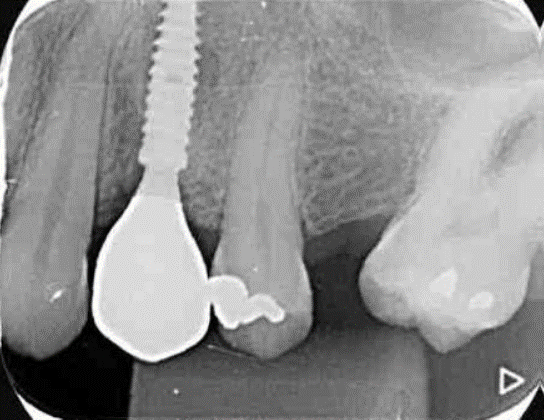

Neste caso relatado a seguir, a fratura do dente 24 levou à indicação de extração atraumática e implante imediato, com uso de biomateriais modernos e fluxo digital completo. O protocolo incluiu implante Due Cone (Implacil Osstem), preenchimento do GAP com Extra Graft, instalação do pilar Ideale definitivo (One Step One Abutment) e posterior coroa em zircônia monolítica.

Após a exodontia do elemento 24 com preservação das paredes ósseas, o preparo foi realizadoseguindo sequência de fresas recomendada para o implante Due Cone, cuja macrogeometriacônica e conexão Morse favorecem alto torque e retenção apical, condições desejáveis para oimplante imediato. A superfície jateada e atacada ao ácido intensifica a adesão celular inicial,contribuindo para osseointegração mais eficiente.

Avaliação inicial da estabilidade — ISQ antes do provisório

Antes da instalação do provisório realizou-se leitura com Osstell, fixando o SmartPegdiretamente no implante recém-instalado. O valor obtido foi ISQ > 70, patamar amplamentedescrito na literatura como favorável para protocolos de carga imediata, desde que associadosa controle oclusal e estabilidade protética. Esse ponto é crucial: a decisão não foi tomada combase apenas no tempo, mas em estabilidade primária real e mensurável, reforçando umaconduta guiada por evidência. Somente após ISQ favorável optou-se por provisório funcional.

Após cerca de 120 dias em função, com perfil gengival consolidado, realizou-se escaneamento intraoral com transferente digital específico sobre o pilar Ideale. O fluxo digital eliminou moldagens analógicas, reduziu etapas e possibilitou desenho preciso do perfil restaurador.

A coroa definitiva foi fresada em zircônia monolítica maquiada, material estável, resistente e com baixa porosidade. Com resistência flexural entre 900–1200 MPa, permite restaurações finas com segurança mecânica e excelente longevidade clínica. A prótese foi parafusada diretamente sobre o pilar Ideale, utilizando o parafuso Torx com torque recomendado de 20 Ncm. O parafuso Torx apresenta tamanho menor em comparação ao parafuso convencional, o que otimiza o espaço interno disponível — especialmente relevante em regiões anteriores ou coroas com menor espessura oclusal. Sua geometria permite maior eficiência na transmissão de torque com menor risco de espanar, além de melhor acoplamento chave/parafuso, conferindo segurança durante a instalação e remoção. A instalação direta sobre o Ideale reduz interfaces, microgaps e micromovimentos, favorecendo selamento marginal mais previsível e estabilidade dos tecidos ao longo do tempo.